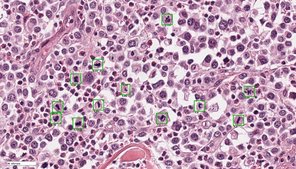

Die Zielsetzung dieses Forschungsprojektes ist es innovative Softwarelösungen unter Einbeziehung von Methoden der künstlichen Intelligenz zu entwickeln und für die diagnostische Anwendung zu validieren. Zusammen mit Kooperationspartners von der Technischen Hochschule Ingolstadt (Arbeitsgruppe Prof. Dr. Marc Aubreville), Friedrich-Alexander Universität Erlangen-Nürnberg (Arbeitsgruppe Prof. Dr. Katharina Breininger), Freien Universität Berlin (Arbeitsgruppe Prof. Dr. Robert Klopfleisch) und Animal Medical Center New York (Dr. Taryn A Donovan) werden verschiedene relevante diagnostische Fragestellungen, insbesondere auf dem Gebiet der Tumorpathologie, bearbeitet. Schwerpunkt sind die Optimierung der Algorithmen, um eine breite Anwendung in verschiedenen Laboren zu ermöglichen, die verschiedenen Anwendungsmöglichkeiten zu erforschen, den Einfluss auf Qualität und Effizienz der Diagnose / Prognose zu untersuchen sowie Vor- und Nachteile bzw. Limitationen der automatisierten Bildanalyse herauszuarbeiten.

Computerisierte Detektion von Mitosefiguren (grüne Kasten) in einem histologischen Präparat eines kaninen Mastzelltumors.